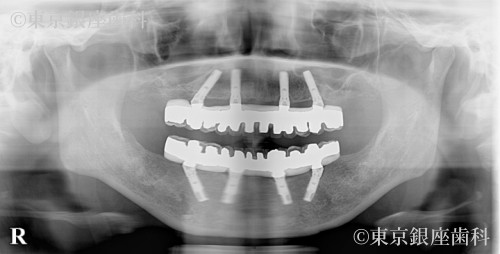

After

重度歯周病と口臭に悩み、抜歯とインプラントで清掃性が改善。口臭も消失し前向きな生活に変化。最終補綴まで約1年半。

上下ワンデイインプラント